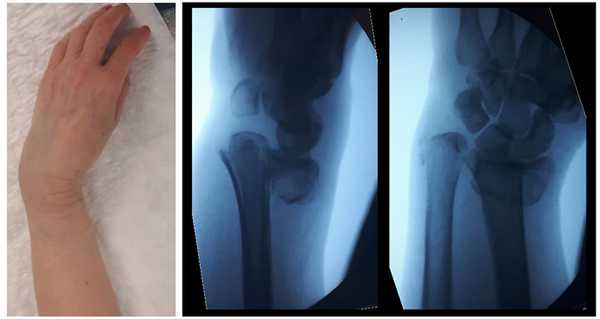

Пациентка М 65 лет, травма в результате падения на улице с опорой на кисть. В анамнезе множественные переломы, миеломная болезнь в стадии ремиссии (7 лет). После падения обратилась в РТП где ей была наложена гипсовая повязка. По какой то причине репозиция не производилась. После обращения в нашу клинику госпитализирована для оперативного лечения.

Внешний вид конечности после снятия гипсовой повязки. Рентгенограммы выполненные при помощи ЭОП на операционном столе выявили полное смещение всего дистального метафиза лучевой кости к тылу на целый поперечник.

Когда имеешь дело с таким переломом на фоне остеопороза становится ясно, что в метафизарной зоне будет «каша» из множества мелких отломков, и что суставная поверхность будет расколота минимум на 3 части.

В такой ситуации требуется надёжная фиксация при помощи пластины с угловой стабильностью, так как риск вторичного смещения в гипсовой повязке крайне высокий. При отказе от операции возможно лечение методом гипсовой иммобилизации, при этом перелом срастётся с небольшим смещением, но в функциональном плане рука будет работать удовлетворительно. По этой причине у пожилых пациентов с низкими функциональными запросами лечение может проводится методом гипсовой иммобилизации.